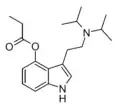

| 4-AcO-DMT | artificial | 4-OCOCH3 | CH3 | CH3 | 4-acetoxy-N,N-dimethyltryptamine | 92292-84-7 |

| 4-PrO-DMT | artificial | 4-OCOCH2CH3 | CH3 | CH3 | 4-propionyloxy-N,N-dimethyltryptamine | 1373882-11-1 |